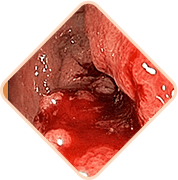

Defekatsiya paytida qon ketishi,

najasda qon izlari.

Gemorroyidal prolapsi

Yod jismlar va og'irlik

hissi mavjudligi

Orqa teshikda qichishish

va achishish

Defekatsiya, yurish yoki

o'tirish paytidagi og'riq

Gemorroyidal tugunlarga

tegilganda og'riq